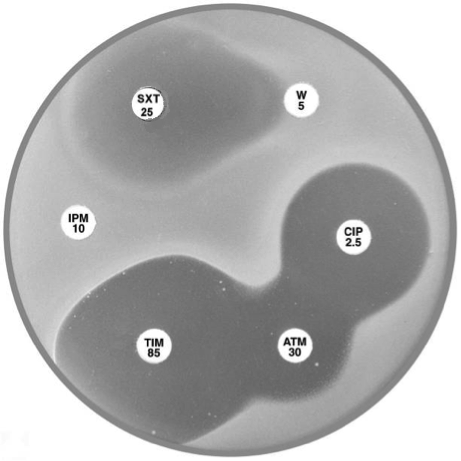

Plate 12.14.A Pseudomonas aeruginosa producing an ESBL Showing synergy between ticarcillin-clavulanic acid (TIM 85) & ceftazidime (CAZ 10) and between piperacillin-tazobactam (TZP 55) & aztreonam (ATM 30). |